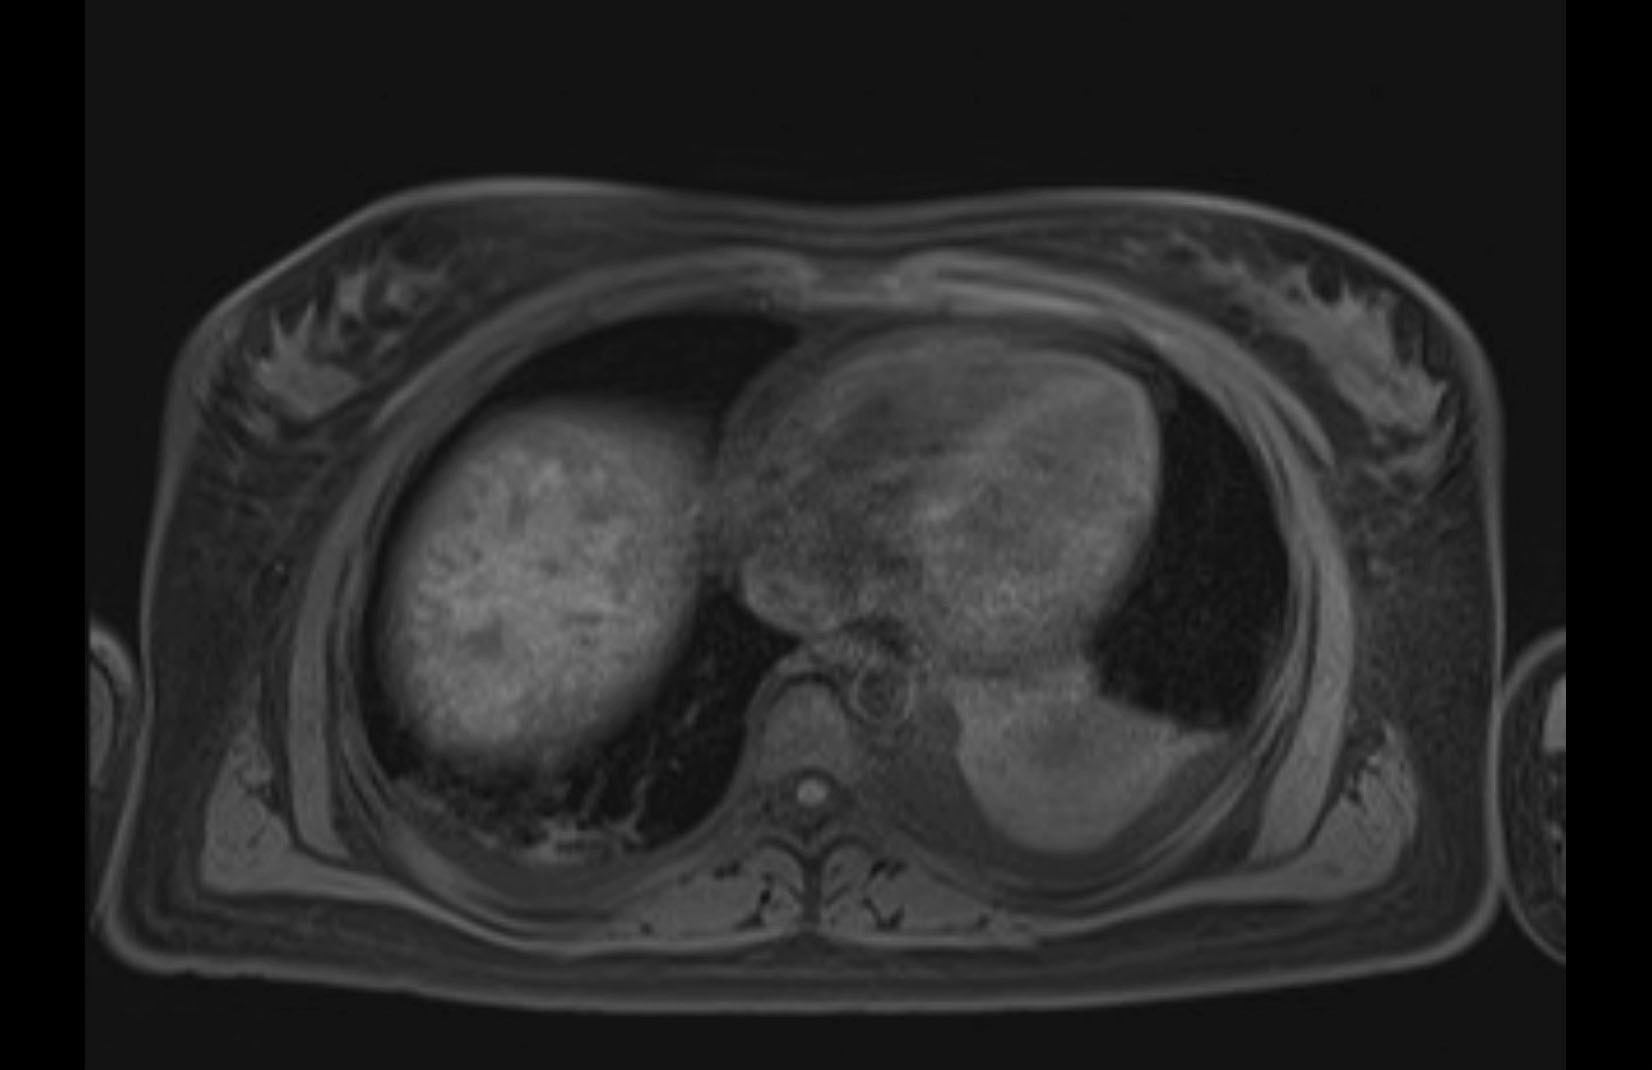

MRI T1

MRI T2

Imaging analysis

Based on initial findings, which issue(s) would you be most concerned about?